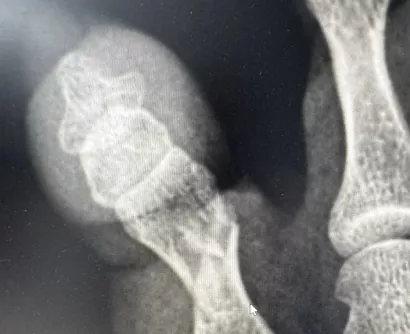

Осмотр и рентгенография позволили поставить диагноз — оскольчатый перелом проксимальной фаланги 5-го пальца. Иван Александрович выполнил репозицию (сопоставление) отломков кости и иммобилизацию стопы гипсовой лангетой. Контрольная рентгенограмма после процедуры позволила оценить результат и убедиться в восстановлении фрагментов. Пациентка довольная уехала домой.

Перелом пятого пальца левой стопы (1) и после репозиции кости и иммобилизации гипсовой лангетой